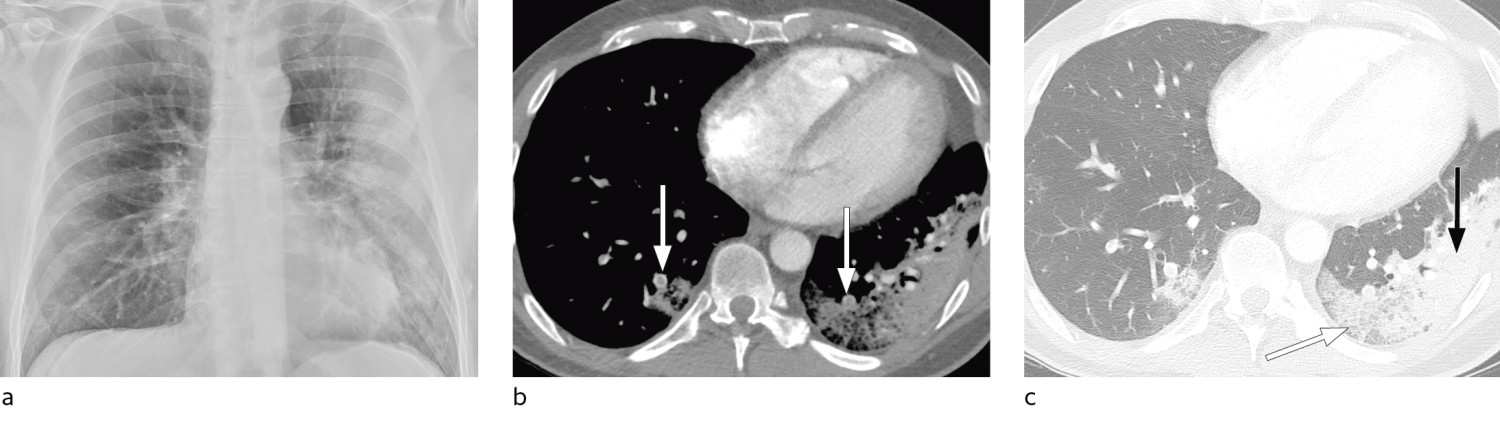

Typical CT findings vary with symptom duration and can be divided into three stages: an early phase, an intermediate phase that extends from 3–5 days after symptom onset, and a late phase.

There are not always CT findings the first few days after symptom onset. In a material with symptomatic, but unspecified patients, 56 % had normal CT findings within two days of symptom onset (12), declining to 9 % 3–5 days after symptom onset and 4 % 6–12 days after symptom onset. The frequency of findings varies with the severity of the disease. Initial diagnostic imaging yielded normal findings for 18 % in a cohort of patients who were not severely ill, but in only 3 % of patients who were (15). Typical CT findings are multiple, bilateral ground-glass opacities with peripheral distribution, most frequently located in the lower lobes. In the intermediate phase there are increasing amounts of consolidation and affection of several lobes, and increased septation with crazy paving as sign of interstitial affection. In the late phase there is increasing total extension, but ground-glass opacities and consolidation are still the dominant findings (12, 16). Figures 4, 5 and 6 show typical CT findings in different phases of COVID-19.

In a severe disease course, distortion of the lung architecture, traction bronchiectasis, enlarged lymph nodes and pleural fluid can be detected. These are findings that are not specific for COVID-19 (17).

In patients with acute respiratory distress syndrome (ARDS), CT can provide useful information about available ventilatable lung volume with a view to optimising ventilation (31, 32), and it can be essential for identifying bullae or pneumothorax. For patients with confirmed COVID-19, CT may be indicated in the event of suspected complications such as pulmonary embolism or superinfection (Figure 7) and for following up unresolved findings on chest X-rays.